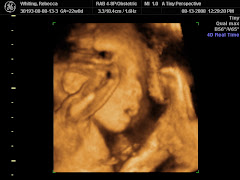

mark!! Becca proclaimed us to be finally readyfor the delivery of our little baby girl. This past week we received the dresser and the changing table at the house and I dutifully put them together. No cursing on my part either!! I do have to say they look great and Becca wasted no time in stuffing them with clothes. She set up a plan to keep all the clothes in order, but we will see how long that lasts, especially when it is the middle of the night and she needs a changing.

Her belly button reminds me of a turkey baster with how far it is poking out, which must mean that Baby Girl is almost done cooking :):) Last night we went on a haunted hayride, and for the record, I was against it!! She was adamant, though, and so we went. I guess my "Bouncer" abilities don't take effect until AFTER the baby arrives. Becca got her baby diaper bag the other day and I am waiting for my quinteesential Ironman diaper bag. (As an aside, the word "diaper" is kinda weird when you think about it. I mean, it isn't spelled the way you would think it should be given the spelling of the word. Just for giggles, I may add in the extra syllable and go for "dy-uh-per"). Things are well here and we are both TRE-mendously excited about the upcoming arrival of baby girl whiting!!